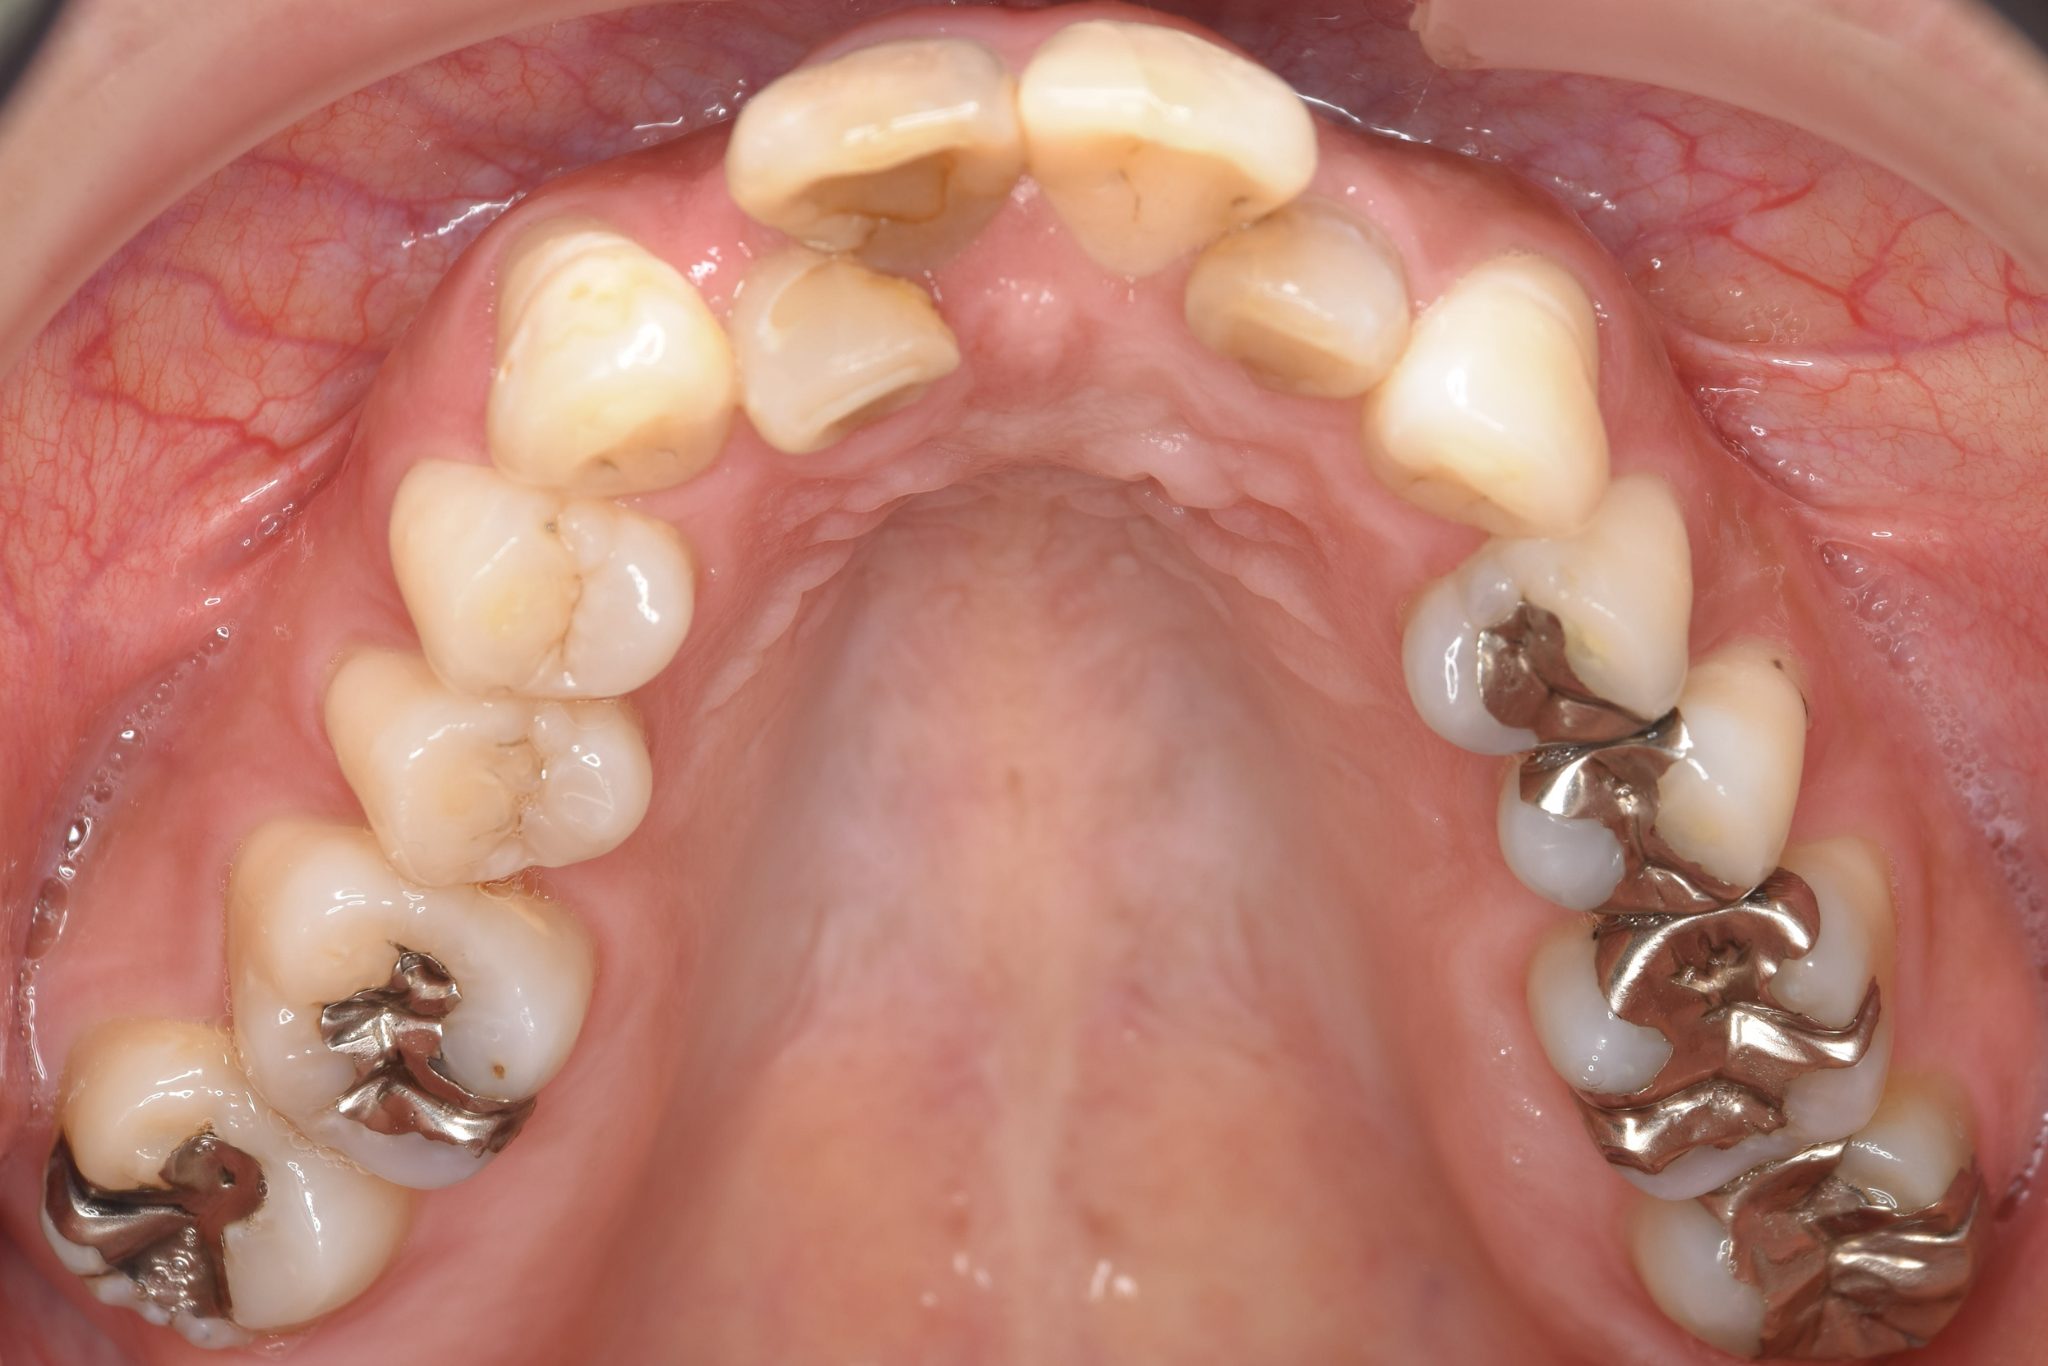

インビザライン矯正治療|症例_649